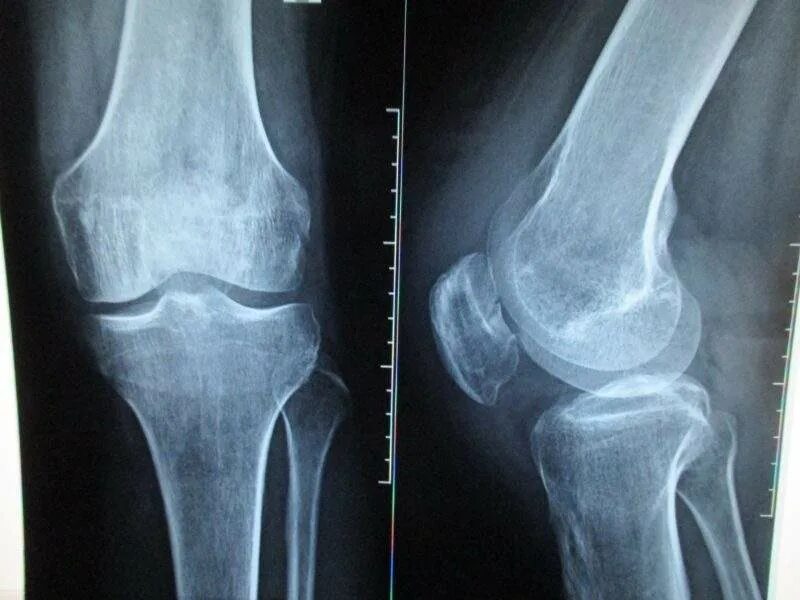

Смещение колена